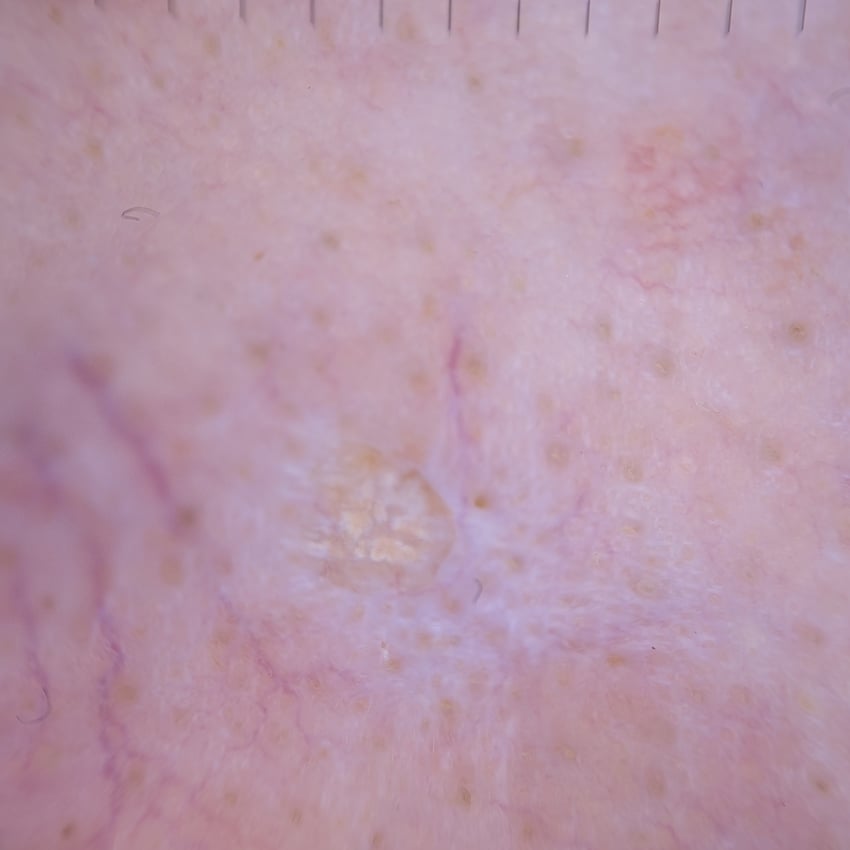

Case discussion: A 50-year-old female had curettage and cautery of an SCC on her nose. A new lesion is arising from within the curettage scar. What next?

This week's case, submitted by Dr David Stewart, features a 50-year-old female patient who attends for her routine skin check.

Two years ago, she had curettage and cautery of a small, well-differentiated squamous cell carcinoma on the right side of her nose. Last year, the site was clear.

Upon examination at today's check-up, a new small lesion is arising from within the curettage scar.

What do you think of it?